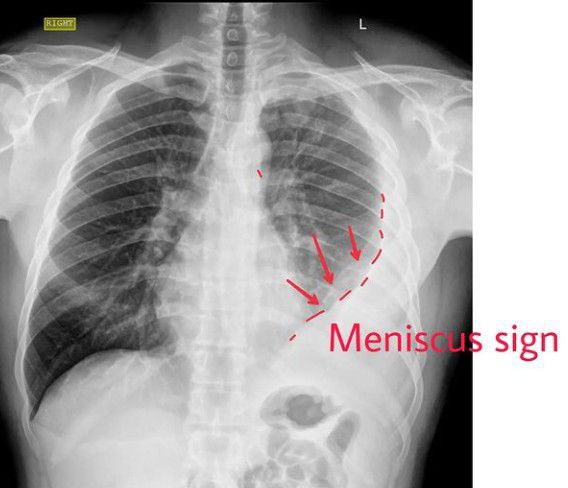

It is the accumulation of fluid in between the parietal and visceral pleura, called pleural cavity. ⠀ ⠀ ✅It can occur by itself or can be the result of surrounding parenchymal disease.⠀ ⠀ ⏩Pleural fluid is classified as a transudate or exudate based on modified Light’s criteria. ⠀ ⠀ ⏩Pleural fluid is considered an exudative effusion if at least one of the criteria are met.⠀ ⠀ ✅Pleural fluid protein/serum protein ratio more than 0.5⠀ ✅Pleural fluid LDH/serum LDH ratio of more than 0.6⠀ ✅Pleural fluid LDH is more than two-thirds of the upper limits of normal laboratory value for serum LDH.⠀ ⠀ ⠀ ⏩Common causes of transudates include conditions which alter the hydrostatic or oncotic pressures in the pleural space like congestive left heart failure, nephrotic syndrome, liver cirrhosis, hypoalbuminemia leading to malnutrition and with the initiation of peritoneal dialysis.⠀ ⠀ ⏩Common causes of exudates include pulmonary infections like pneumonia or tuberculosis, malignancy, inflammatory disorders like pancreatitis, lupus, rheumatoid arthritis, post-cardiac injury syndrome, chylothorax (due to lymphatic obstruction), hemothorax (blood in pleural space) and benign asbestos pleural effusion.⠀ ⠀ ⠀ ⏩A patient with pleural effusion can be asymptomatic or can present with exertional breathlessness depending on the impairment of thoracic excursion. ⠀ ⠀ ✅Patient with active pleural inflammation called pleurisy complains of sharp, severe, localized crescendo/ decrescendo pain with breathing or a cough.⠀ ⠀ ✅The physical examination can be subtle. In large effusion, there will be the fullness of intercostal spaces, and dullness on percussion on that side. ⠀ ⠀ ✅Auscultation reveals decreased breath sounds and decreased tactile and vocal fremitus.⠀ ⠀ ✅Egophony is most pronounced at the superior aspect of the effusion.⠀ ⠀ ✅Pleural rub, often mistaken for coarse crackles can be heard during active pleurisy without any effusion By: https://www.instagram.com/p/CebZPljhR0V/?igshid=YmMyMTA2M2Y=